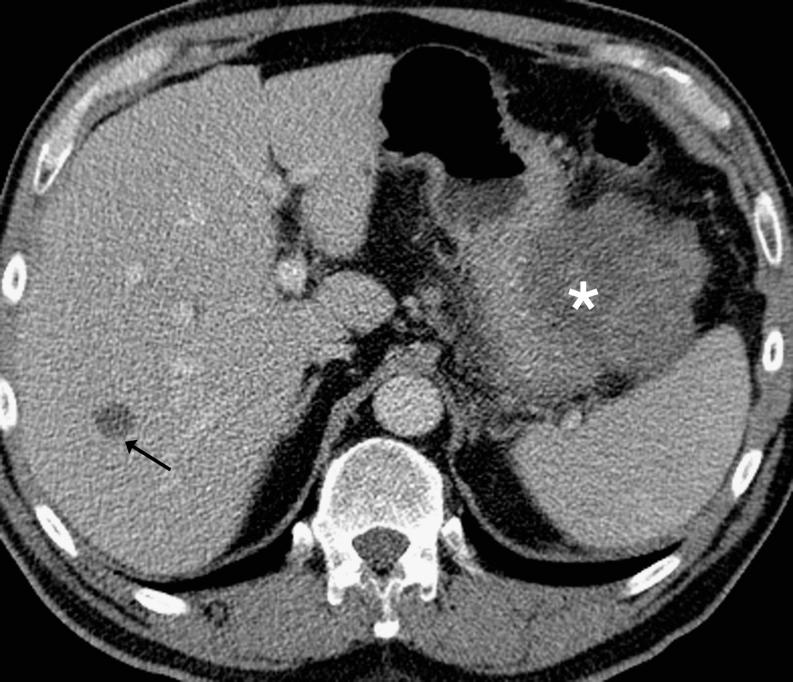

腹部和骨盆常见原发性肿瘤及其在多排螺旋计算机断层扫描上显示的肿瘤扩散模式。

Common primary tumours of the abdomen and pelvis and their patterns of tumour spread as seen on multi-detector computed tomography.

多排螺旋计算机断层扫描(MDCT)已成为许多癌症分期的主要首选检查方法。目的:本影像综述的目的是讨论腹部和盆腔内一些较常见癌症的CT影像表现,并描述其局部、淋巴结及血行肿瘤转移的典型部位。方法:将对源自胃、胰腺、结肠、肾、卵巢和前列腺的癌症进行综述。结果:了解肿瘤转移的特征部位对于准确识别所有疾病部位很重要。结论:这显然会对患者的治疗和预后产生影响。